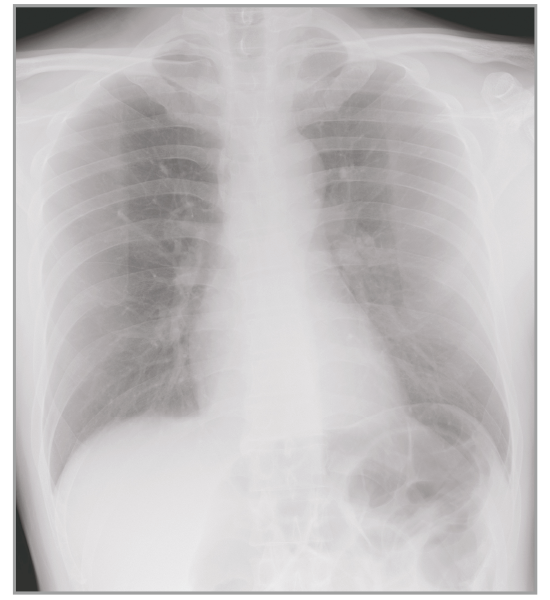

Multiple body parts supported

Abdomen

Dynamic Visualization II

Optimizes image quality using latest Exposure Data Recognizer

Advanced recognition algorithms using automatic  calculations of estimated 3D image data, identify the body part required and adjusts contrast, density and enhancement for optimised image display. (Option)